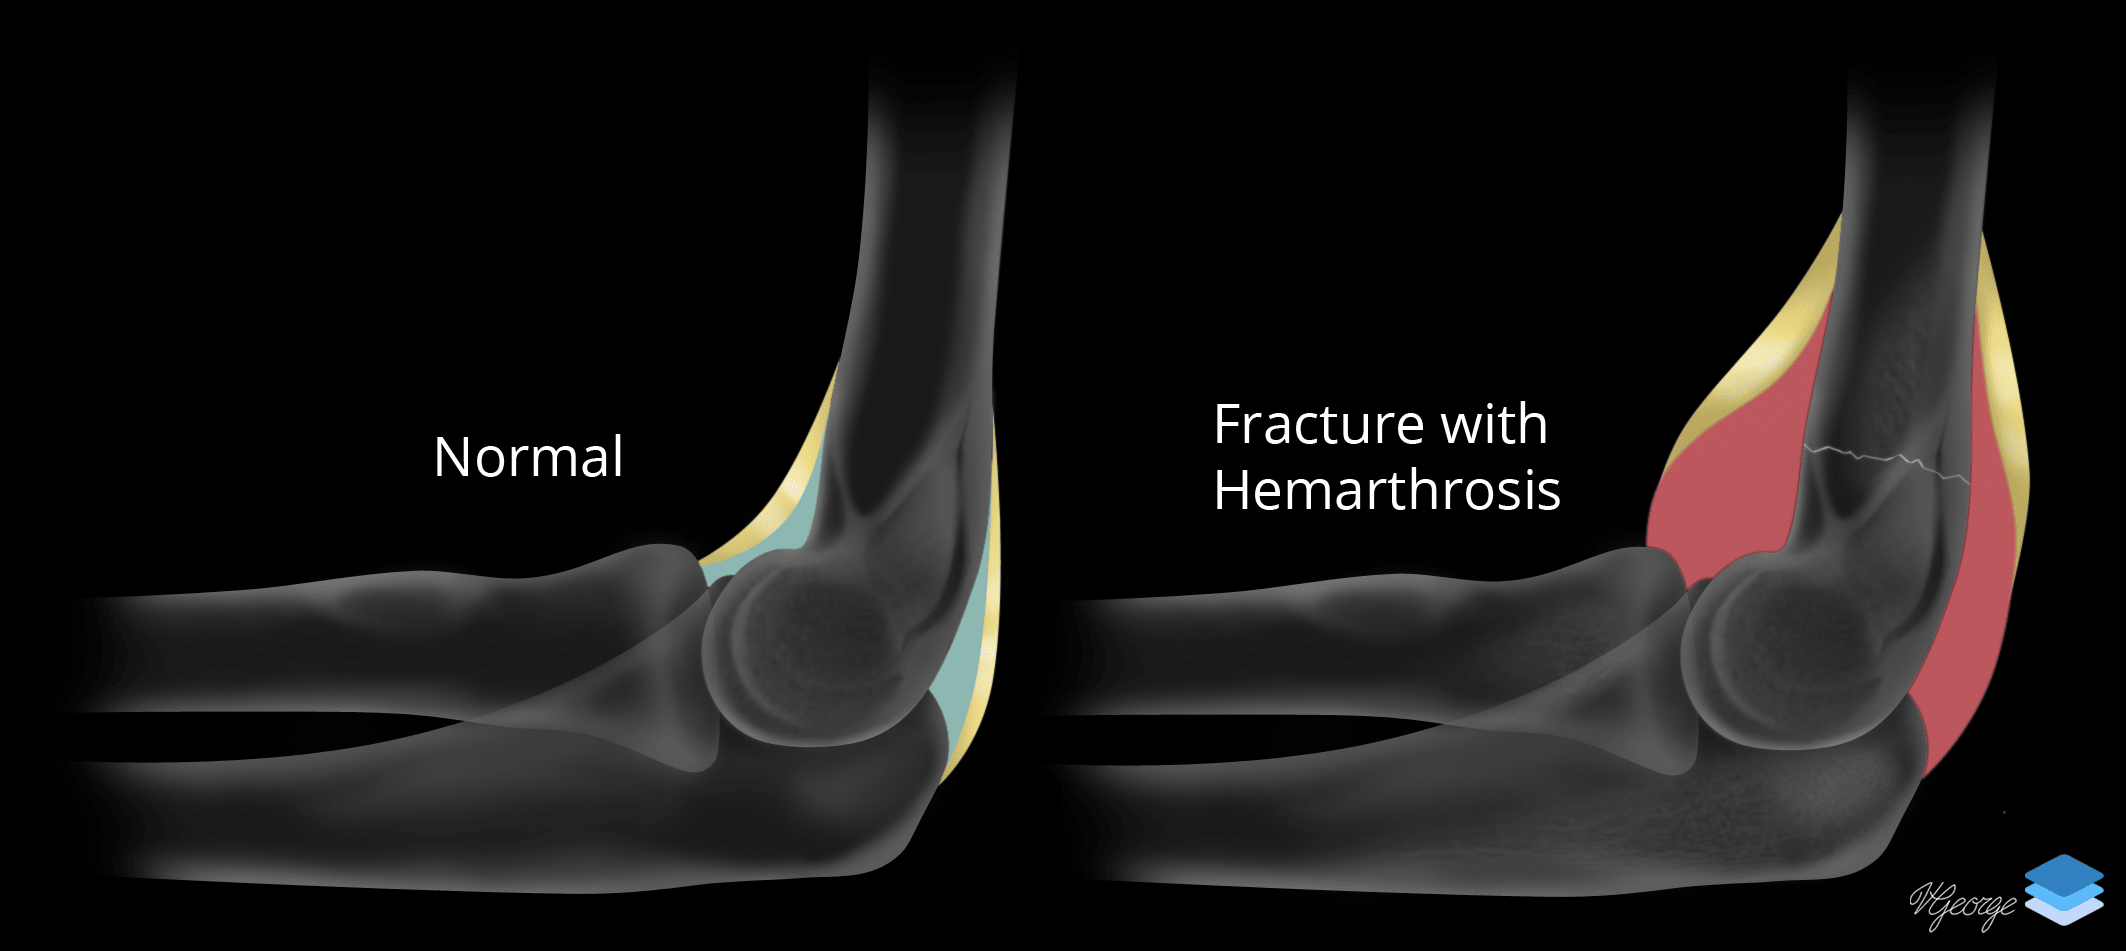

Elbow joint effusion. Illustration by Valerie George, MD

- Also, if you see an elbow joint effusion in a child but do not see a fracture, bring up the possibility of a supracondylar fracture and recommend follow-up radiographs in 1-2 weeks to look for healing changes

- Elbow joint effusion